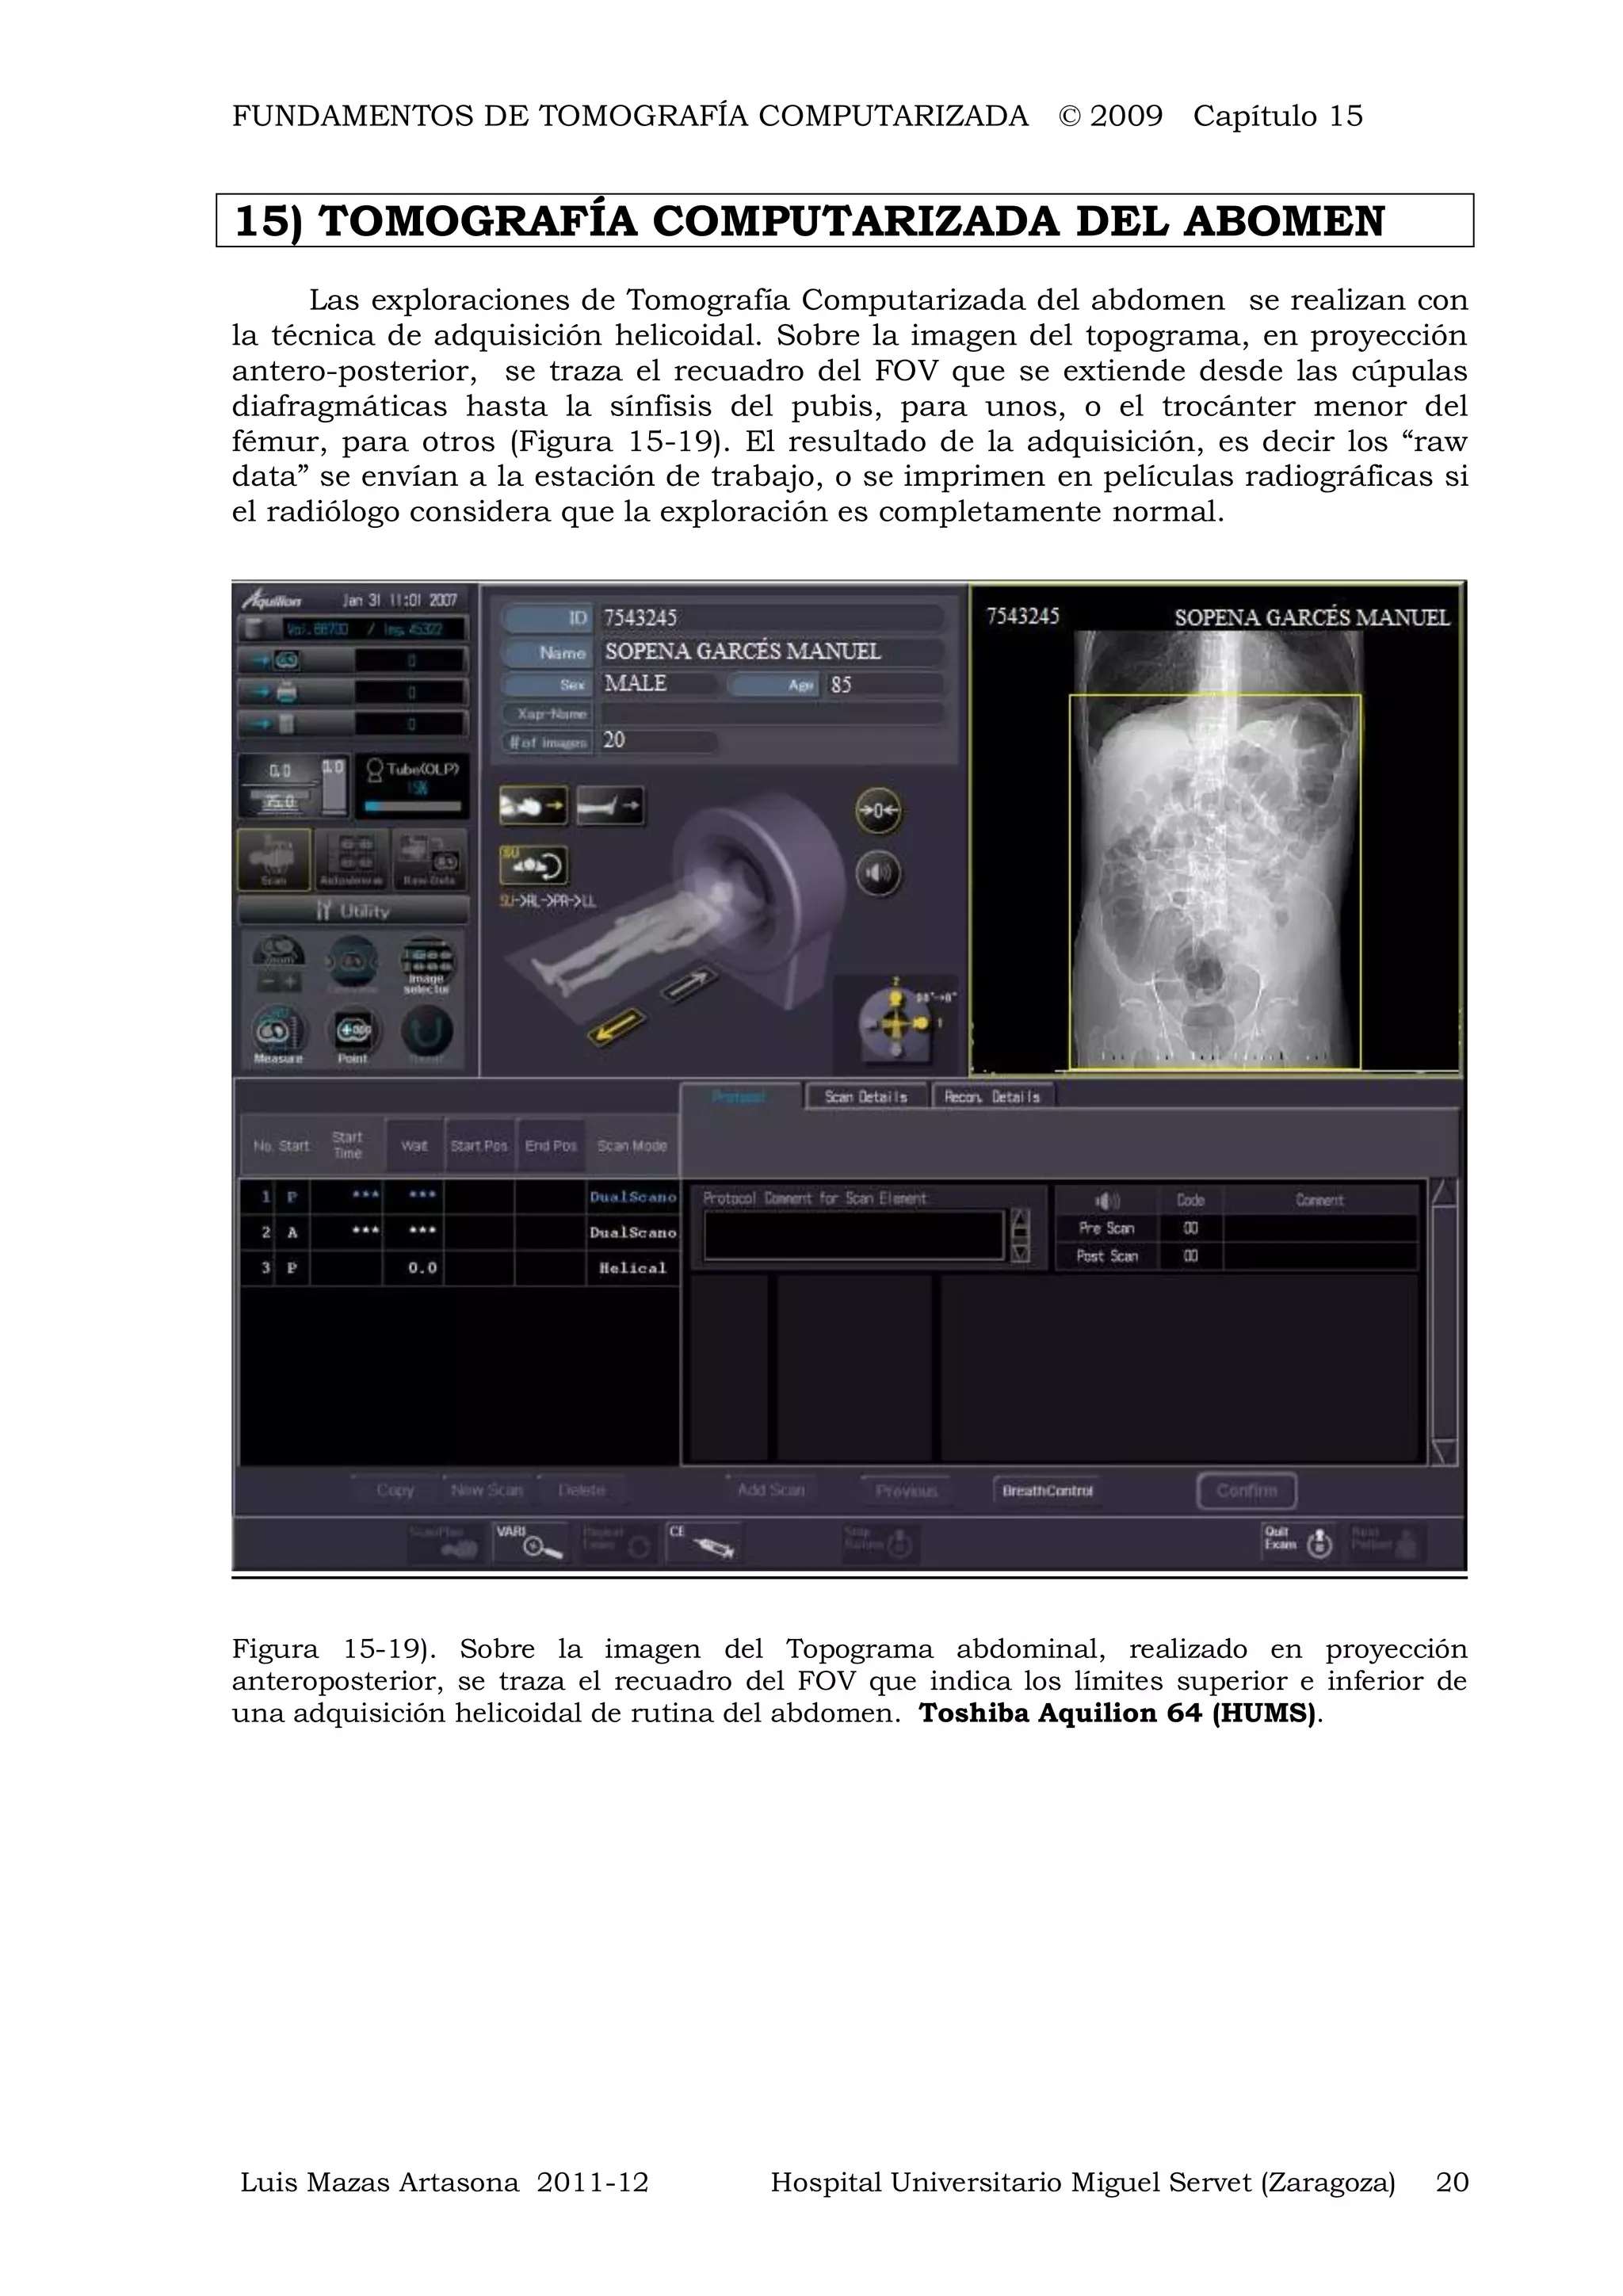

Las exploraciones de Tomografía Computarizada del abdomen se realizan con

la técnica de adquisición helicoidal. Sobre la imagen del topograma, en proyección

antero-posterior, se traza el recuadro del FOV que se extiende desde las cúpulas

diafragmáticas hasta la sínfisis del pubis, para unos, o el trocánter menor del

fémur, para otros (Figura 15-19). El resultado de la adquisición, es decir los “raw

data” se envían a la estación de trabajo, o se imprimen en películas radiográficas si

el radiólogo considera que la exploración es completamente normal.

Figura 15-19). Sobre la imagen del Topograma abdominal, realizado en proyección

anteroposterior, se traza el recuadro del FOV que indica los límites superior e inferior de

una adquisición helicoidal de rutina del abdomen. Toshiba Aquilion 64 (HUMS).